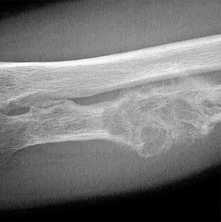

(Справа) Рентгенография в ЗП проекции: определяется типичная картина трубчатых костей кисти при талассемии, при которой наблюдается преобладание гиперплазии костного мозга. Все кости приобретают квадратную форму или теряют нормальную форму, что обусловлено накоплением костного мозга. (Слева) Рентгенография бедренной кости ребенка в ПЗ проекции: определяется нарушение формирования нормальной полости в дистальном метафизе. Это напоминает картину по типу колбы Эрленмейера при болезни Гоше, являющейся болезнью накопления. В этом случае костный мозг упакован в кроветворные ячейки.

(Справа) Рентгенография нижней конечности в ПЗ проекции: определяется некоторое истончение кортикальной пластинки, квадратная форма и уменьшение полости кости, что согласуется с замещением костным мозгом при талассемии. Интересно то, что инфаркты кости при этом заболевании встречаются намного реже, чем при серповидноклеточной анемии.